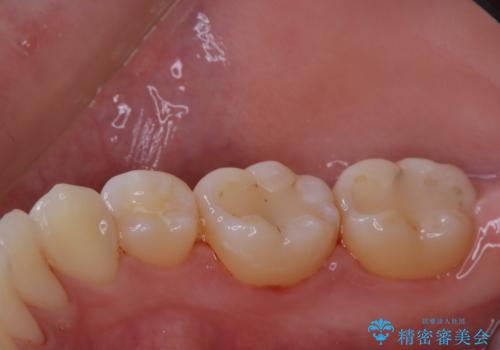

治療の前にPMTCできれいでツルツルな歯に

- 今後治療を進めていく予定で、まずはきれいにクリーニンングから行いたいとのことでした。PMTC60分コースを行いました。